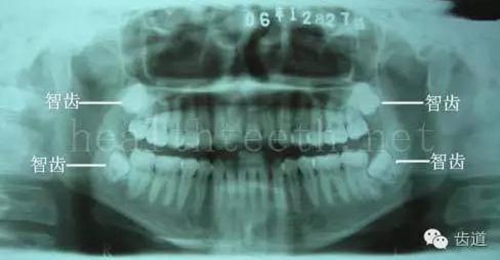

九、關(guān)于智齒(第八顆牙)

四顆長不出來的智齒

80.jpg

智齒反復(fù)發(fā)炎造成的頰瘺,膿腫切開引流后面部會留疤

81.jpg

智齒造成的頜骨囊腫,手術(shù)切除后需要植骨